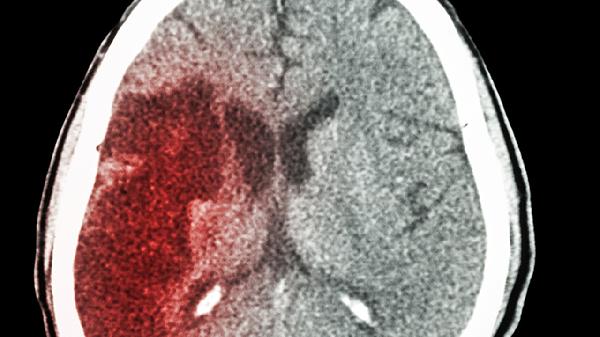

叶酸参与一碳代谢,有助于维持血管弹性。充足的叶酸能改善脑部供血,减少微小血栓形成。

作为甲基供体,叶酸能减轻氧化应激对神经细胞的损伤。这种保护机制对预防血管性痴呆尤为重要。